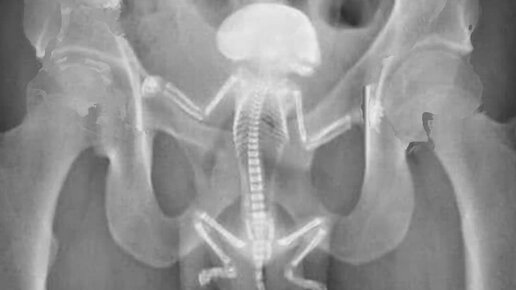

Что это может быть?